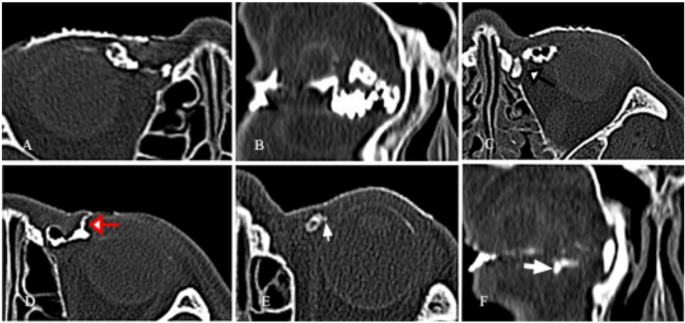

In the canaliculitis group, all patients presented with unilateral eye involvement. The lower canaliculus was more frequently affected (91, 72.2%). Eleven patients (8.7%) had involvement of both the superior and inferior canaliculi. Four patients exhibited cutaneous fistulae in the lacrimal sac region, with visible secretions overflowing from the fistulae. Discharge, concretions, and granulation tissues expressed from the canaliculi or collected during surgery were sent for microbiological evaluation and histopathologic staining. Microbiological culture results were positive in 53 canaliculi from 53 eyes (42.1%) out of 126 eyes, including: Streptococcus species in 23 eyes (18.3%), Actinomyces species in 15 eyes (11.9%), Staphylococcus species in 12 eyes (9.5%), as well as nonspecific Gram-positive organisms, Proteus mirabilis, and Bacillus species occurring in 1 eye each. Histopathological examination of concretions using Gomori methenamine silver staining and Giemsa staining revealed Actinomyces species in 20 canaliculi from 16 eyes (Fig. 1G and H). The remaining cases were definitively diagnosed by detecting concretions or granulation tissues during surgery or dacryoendoscopy.

Dacryoendoscopic examination, intraoperative and histological findings of primary canaliculitis. (A) Dacryoendoscopy showing concretions in the central lumen of canaliculi and canalicular dilation. (B) Fragmental concretions in close proximity to the canalicular lumen wall. (C) Concretions at the distal end of the canaliculus close to the common canaliculus. (D) Granulation tissue in the canaliculus lumen. (E) Concretions scraped from the dilated vertical segment of the canaliculus. (F) Concretions detected during canaliculotomy. (G) Giemsa staining of concretions showing blue hyphae and colonies (magnification ×400). (H) Gomori methenamine silver stain showing black hyphae and colonies (magnification × 400). Histological examination revealing typical features of Actinomyces infection. The features are described as interwoven hyphae at the center and radially arranged club-shaped long hyphae at the periphery.

Subsequent dacryoendoscopic examination revealed that the 110 filling defects in affected canaliculi corresponded to 108 concretions and 2 granulation tissues (Fig. 1A-D). All cases with filling defects were accompanied by varying degrees of lacrimal canalicular dilation. Meanwhile, canaliculi with beading changes were found to contain multiple focal lesions, predominantly concretions.